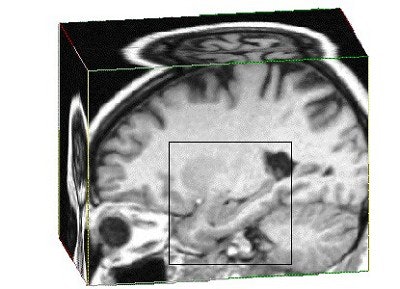

![]() |

| Three-dimensional MR image sectioned to reveal the hippocampus (highlighted by the box), which is approximately 10% smaller in patients with a history of depression. Sheline YI, Gado MH, Kraemer HC, "Untreated depression and hippocampal volume loss," American Journal of Psychiatry, Vol. 160:6, pp. 1516-1518, August 1, 2003. |